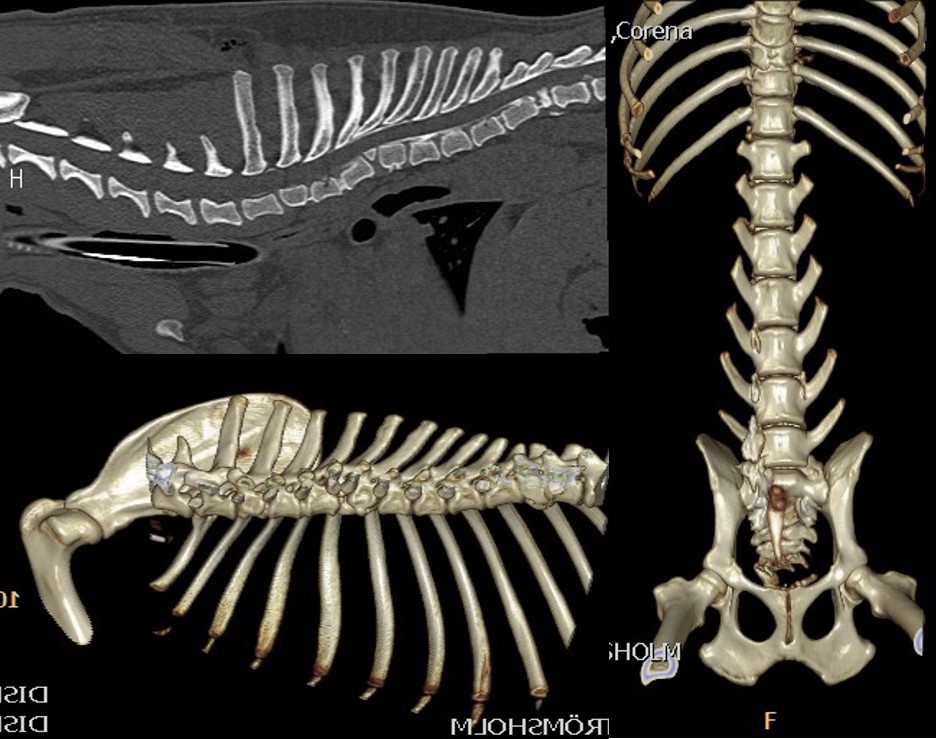

At our hospital we see cat patients after sustaining a trauma. They can have spinal fractures (Fig 1). But because cats have normally a very elastic body, they bend the spine during the trauma until the disk ruptures with a traumatic disk extrusion as consequence. The damage to the spinal cord can be severe, but in most cases a surgery would not help. The MRI is the only diagnostic tool to clearly diagnose such a traumatic extrusion (Fig 2). Fractures to the sacrum and the first vertebra of the tail are also typical for cats. The nerves to the bladder are often damaged in these patients, so the cat has to be in the hospital to ensure the treatment of bladder and fracture (Fig 3).

Fig 1 Fig 2

Fig 1 Fig 2